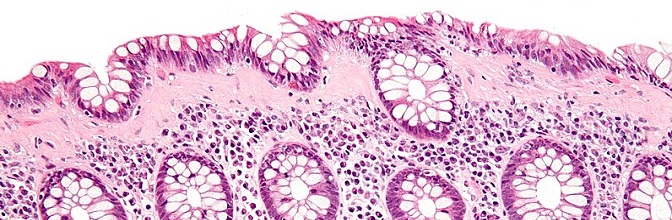

Cechy cytologiczne: Gruczoły szyjki macicy wyścielone są przez nieprawidłowe, kolumnowatego kształtu komórki gruczołowe (Fot. 1). Pod względem cytologicznym przypominają one raka gruczołowego inwazyjnego. Ich jądra komórkowe są hiperchromatyczne, wydłużone, cygarowatego kształtu i posiadają grube ziarnistości chromatyny. Stosunek jądrowo-cytoplazmatyczny przesunięty jest na rzecz jądra. W cytoplazmie występują złogi śluzu wewnątrzkomórkowego (Fot. 2). Patologiczne figury podziałów mitotycznych… Dowiedz się więcej: Gruczolakorak in situ szyjki macicy (łac.: adenocarcinoma in situ [AIS] colli uteri) - Pracownia Genetyki i Biologii Molekularnej